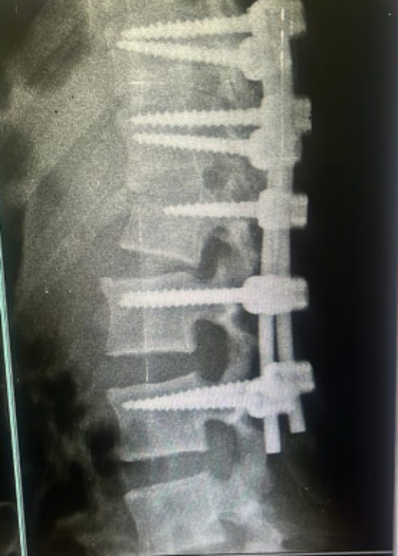

Stabilization

Rods, screws, or cages are used to restore alignment and protect the spinal cord.